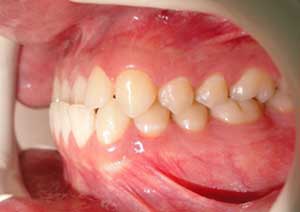

Par la suite, ces cales ont été déplacées sur les faces palatines des incisives maxillaires dans le but d’optimiser l’articulé postérieur, notamment au niveau des molaires droites, qui présentaient également un articulé inversé.

Avant